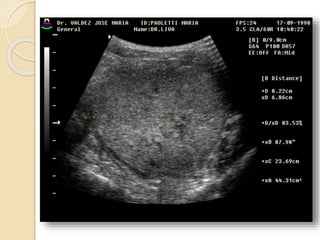

Ecografia tocoginecologica